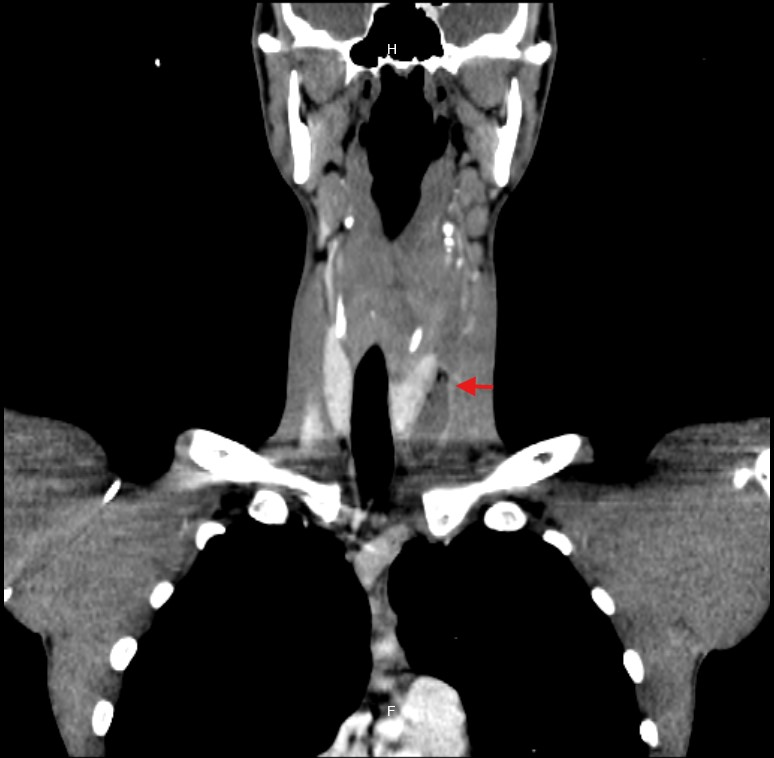

Due to the unclear etiology of the symptoms, combined with unremarkable initial studies and the subsequent development of dyspnea, a CT scan of the neck and thorax was performed. This revealed a large collection centered in the mediastinum, dissecting tissue planes and extending below the carina, reaching into the neck up to the left thyroid lobe. Gas was observed both within the collection and around the thyroid gland and mediastinum, with the esophagus displaced to the right by the mass effect of the abscess (Figure 1-5).

Figure 3 CT: Coronal view showing abscess in the left thyroid space.